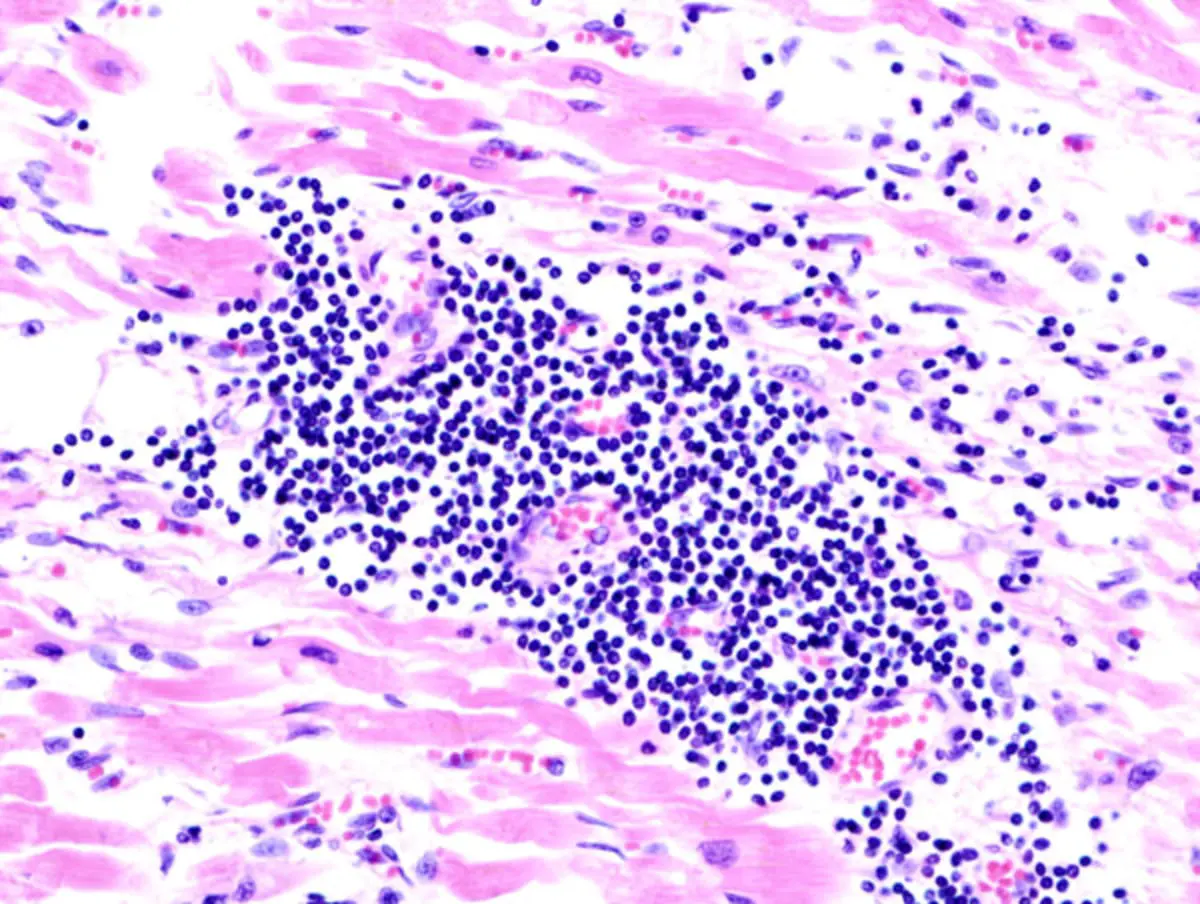

Миокардит — воспалительное поражение сердечной мышцы, возникающее после инфекций или иммунных сбоев. Болезнь крайне сложна для неинвазивного выявления: надежных лабораторных тестов для точного диагноза до сих пор нет. Биопсия миокарда — золотой стандарт, но она инвазивна и применяется редко. Популярные маркеры, такие как тропонин и С-реактивный белок, при миокардите часто в норме.

В проекте участвовали 99 человек. У 50 подтвердили миокардит, у 49 были невоспалительные сердечные заболевания. Специалисты измеряли уровни свободных легких цепей каппа-типа и лямбда-типа. Эти показатели соотносили с симптомами сердечной недостаточности и биомаркерами повреждения сердечной мышцы.